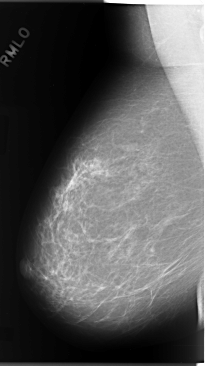

C_0106_1.RIGHT_MLO

RIGHT_MLO LINES 5848 PIXELS_PER_LINE 3280 BITS_PER_PIXEL 12 RESOLUTION 50 NON_OVERLAY